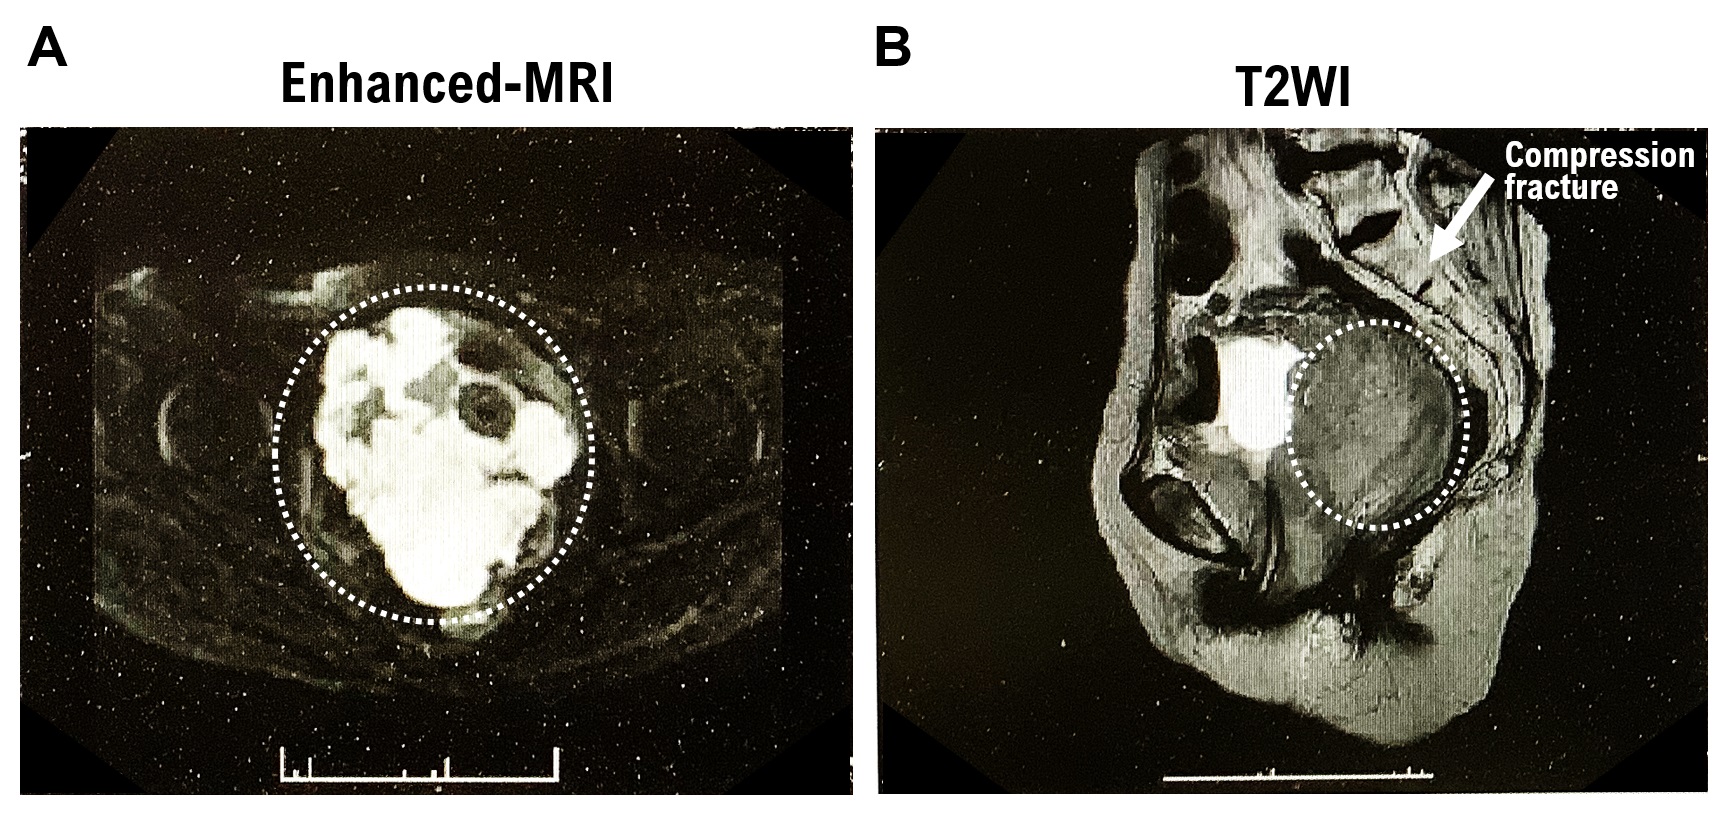

3.1. Contrast-Enhanced MRI Imaging Results

A tumor was observed occupying the area from the urethra to the bladder wall and from the vagina to the uterine vagina. Contrast-enhanced MRI T2W1 imaging results showed a homogeneous, moderate signal (Supplementary Figure S1A). In addition, chronic compression fractures of the thoracic and lumbar spines were observed. Contrast-enhanced MRI (DW1) revealed severe diffusion restriction (Supplementary Figure S1B). Based on the extent of the lesion and signal, the mass was considered to be either a uterine leiomyosarcoma or malignant lymphoma. The rectum was compressed by the mass. However, no evidence of tumor invasion was observed in the rectal wall. Bilateral hydronephrosis and hydroureter formation occurred due to tumor progression. Left ureteral stones, left kidney stones, and left kidney atrophy were observed. Lymphadenopathy was not observed.

1. At the time of initial onset, myeloid sarcoma is often accompanied by malignant myeloid tumors such as AML. However, AML was not detected in this patient. The image shows the macroscopic appearance of a tumor in the cervical tissue. Subendometrial tumors are circled in white dotted lines. The tumor has grown from the uterine body to the cervix (Supplementary Figure S1C,D).

3. The surgical pathological diagnosis performed in this case did not reveal any findings suggesting the development of benign tumors (leiomyoma) or malignant uterine mesenchymal tumors, such as uterine leiomyosarcoma (Figure 1A,B, Supplementary Table S2).